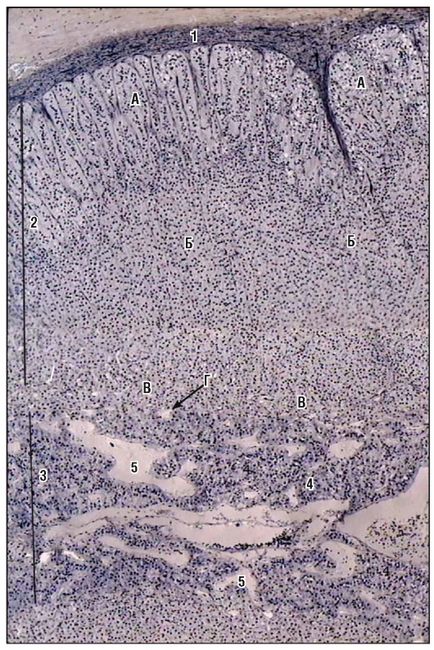

Fig. 171. Nadbochechnik (colorare cu hematoxilină și eozină, creștere mică): 1 - capsulă de țesut conjunctiv; 2 - substanță corticală: zona A - glomerulară; B - zona fasciculului; B - zona ochiurilor de plasă; D - capilare din zona reticulară; 3 - substanța creierului; 4 - celule de cromafină; 5 - vasele de sânge ale măduvei

Fig. 172. Nadbochechnik (colorare cu hematoxilină de fier, o creștere mică): 1 - capsulă de țesut conjunctiv; 2 - substanță corticală: zona A - glomerulară; B - zona fasciculului; B - zona ochiurilor de plasă; D - capilare din zona reticulară; 3 - substanța creierului; 4 - celule de cromafină; 5 - vasele de sânge ale măduvei